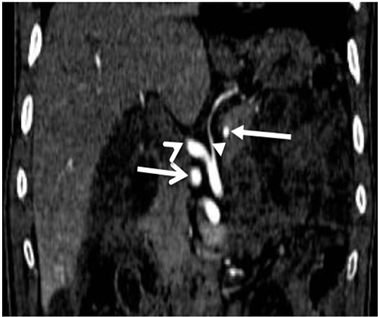

Figure 7. MIP image of enhanced abdominal CT-scan, in frontal section showing a quadrifurcation of celiac trunk, with a right hepatic artery (short arrow), a left hepatic artery (“delta wing”), a stomachic coronary artery (arrow head) and a splenic artery (full arrow).

of two right hepatic arteries and the splenic artery (Figure 8), a “pseudo-arc” of Buhler, stretched between the celiac trunk and the inferior mesenteric artery (Figure 9). Table 2 summarizes all the AVs encountered with their frequencies.